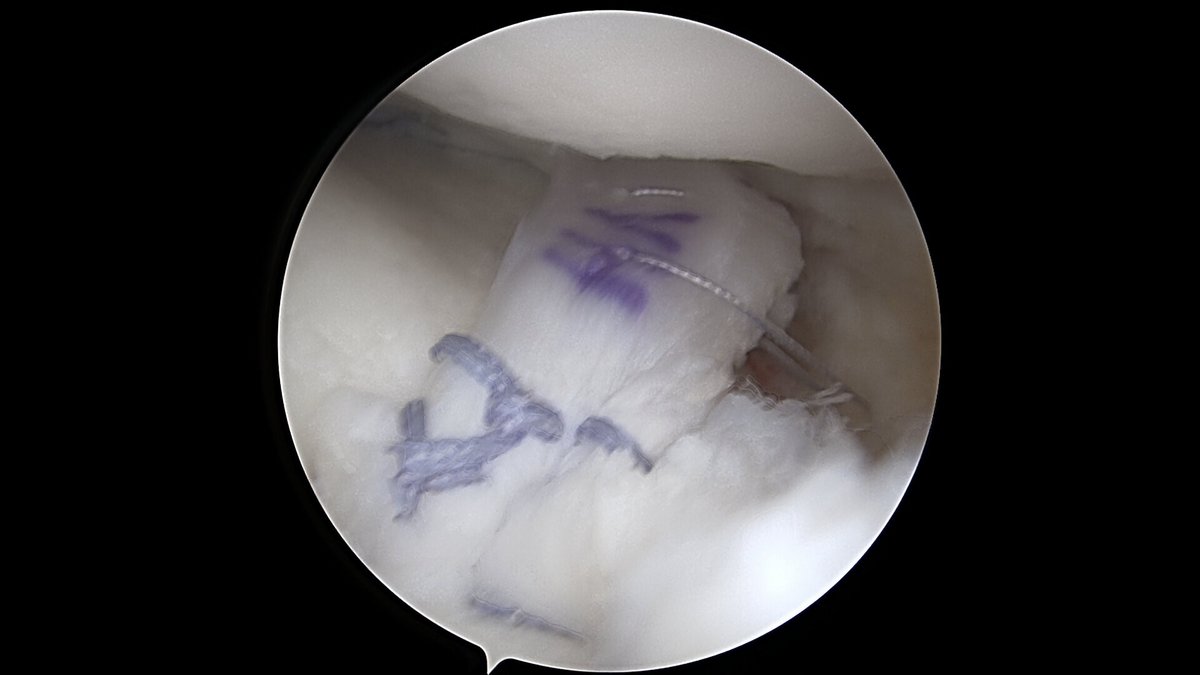

Eine der häufigsten Sportverletzungen im Bereich des Kniegelenkes ist die vordere Kreuzband-Ruptur. Vor allem bei jungen, sportlich aktivem Patienten ist oftmals eine sogenannte VKB-Ersatzplastik notwendig. Goldstandard ist der Ersatz des gerissenen Kreuzbandes durch eine körpereigene Sehne, ggf. können noch stehende Restfasern als Leitstruktur belassen werden. Hierzu stehen verschiedene Transplantate zur Verfügung (Hamstring-Sehnen, Quadrizepssehne, …) die individuell ausgewählt werden. Zusatzverletzungen des Meniskus oder der Seitenbänder werden ebenfalls im Rahmen der Operation behandelt. Das Kreuzband wird über Bohrkanäle an die anatomische Position gebracht und dort mittels sog. Interferrenzschrauben im Kanal verblockt.

Als Behandlungsmöglichkeiten für Knorpelschäden gibt es die sog. Abrasionschondroplastik / Mikrofrakturierung, bei der der defekte Knorpel bis auf den Knochen abgetragen und dieser dann mit kleinen Löchern perforiert und ggf. mit einer speziellen Membran bedeckt wird. Durch die Perforationen tritt Knochenmark in den Defekt ein und es bildet sich ein sog. Regeneratknorpel. Auch die Möglichkeit einer Knorpelzelltransplantation (sog. „ACT“) wird bei uns angeboten. Hier werden in einer ersten Operation Knorpelzellen entnommen und in einer zweiten Operation in den Defekt eingebracht (entweder als sog. ACT Inject in einer Suspension oder als ACT 3d auf einer Membran). Auch die körpereigene Transplantation eines Knochen-Knorpel-Zylinders (OATS / Mosaikplastik) ist eine Therapiemöglichkeit, die wir anbieten können.